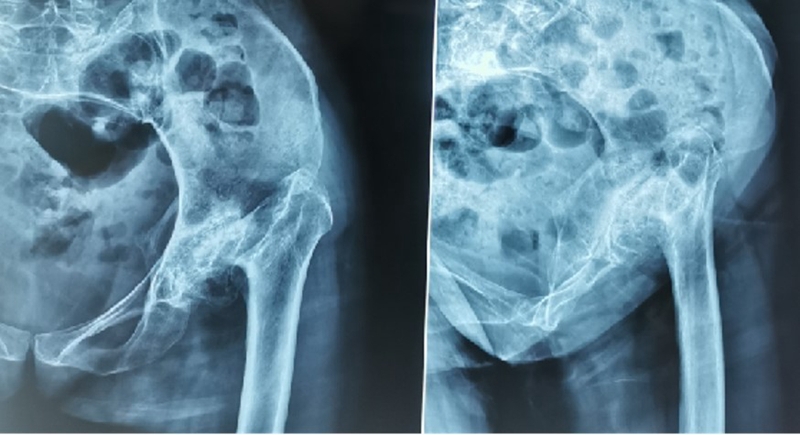

硬化骨、骨赘、骨质疏松、髓腔宽大

转子间骨折畸形愈合后常导致干骺端畸形,干骺端遗留大量硬化骨或髓腔成角,术中需在确认髓腔开口位置后,首选用小骨刀或高速磨钻去除硬化骨,打通髓腔。

干骺端畸形还可引起髓腔增宽,骨量减少,骨质疏松,不能为近端压配固定型的假体提供良好稳定。宜选用全微孔涂层远端固定假体。